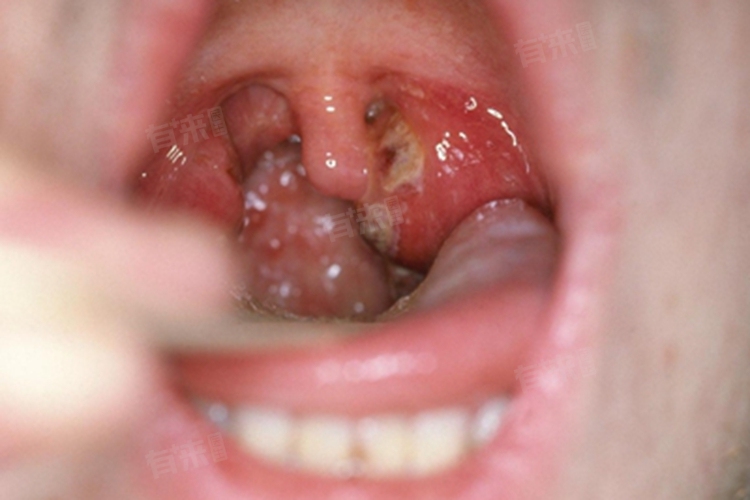

咽喉化脓的恢复时间因人而异,通常在7-14天,但受到多种因素的影响。咽喉化脓一般是由细菌或病毒感染引起,如链球菌、葡萄球菌、腺病毒等。感染的严重程度、患者的个体免疫力、治疗的及时性和有效性等都会影响恢复时间。

- 如果感染严重,病原体毒力强,或者患者免疫力低下,如患有糖尿病、营养不良、长期使用免疫抑制剂等,恢复时间可能会延长,可能需要10-14天甚至更长时间。严重的咽喉化脓可能导致全身性症状,如高热、寒战、乏力等,治疗难度也相应增加。

- 治疗方法的选择也会影响恢复时间,如果单纯依靠药物治疗效果不佳,可能需要进行局部的穿刺引流或手术切开排脓,这会延长恢复的进程。患者在治疗期间的护理和生活方式也至关重要,过度用嗓、吸烟、饮酒、劳累、睡眠不足等不良因素都可能延缓恢复。